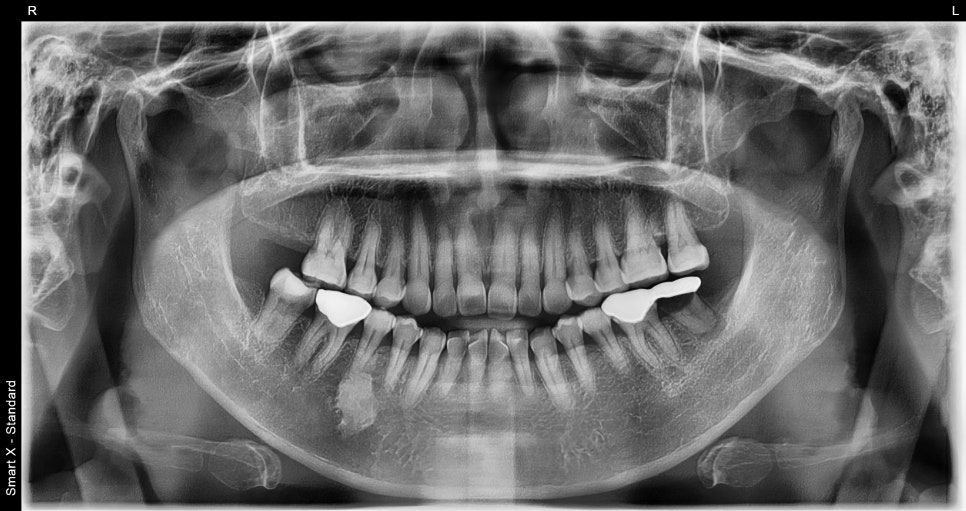

A patient in their 50s who visited with a molar issue

This patient came in for scaling

and during the visit, the condition of the molar was checked.

There had been a prosthetic restoration on the existing molar, but the prognosis was poor,

so extraction was ultimately necessary.

Molars may look fine from the outside,

yet the internal condition is often not good.

In particular, when there is an old prosthetic restoration, it can lead to a situation

where retreatment or an implant is needed.

Implant surgery performed at the same time as extraction

In this case, the implant was placed immediately after the molar extraction.

✔ First implant surgery

✔ Guided bone regeneration performed

✔ Allograft bone graft performed in combination